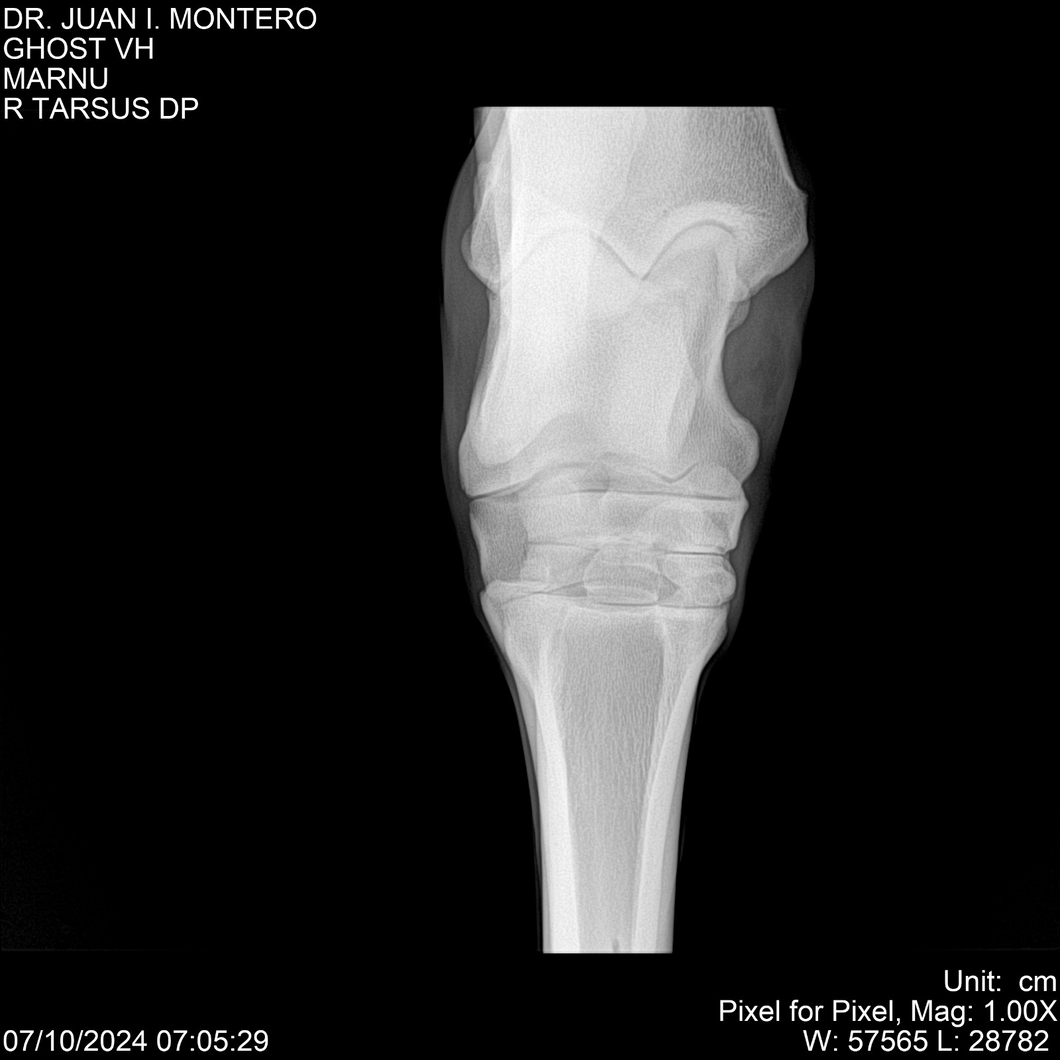

LOTE 15, GHOST VH 🔥 🔥 🔥 Lote Anterior Volver al remate Lote Siguiente Ficha Contacto Montevideo - Ficha del Lote Identificador: #282525 Categoría: Yeguarizos Montevideo - 69 Visualizaciones ClicData Contacto Empresa: Abelenda N. R., Walter Hugo Nombre*: Teléfono* : E-mail* : Mensaje Enviar Registrese gratis Este contenido Exclusivo está disponible sólo para usuarios registrados Ingresar